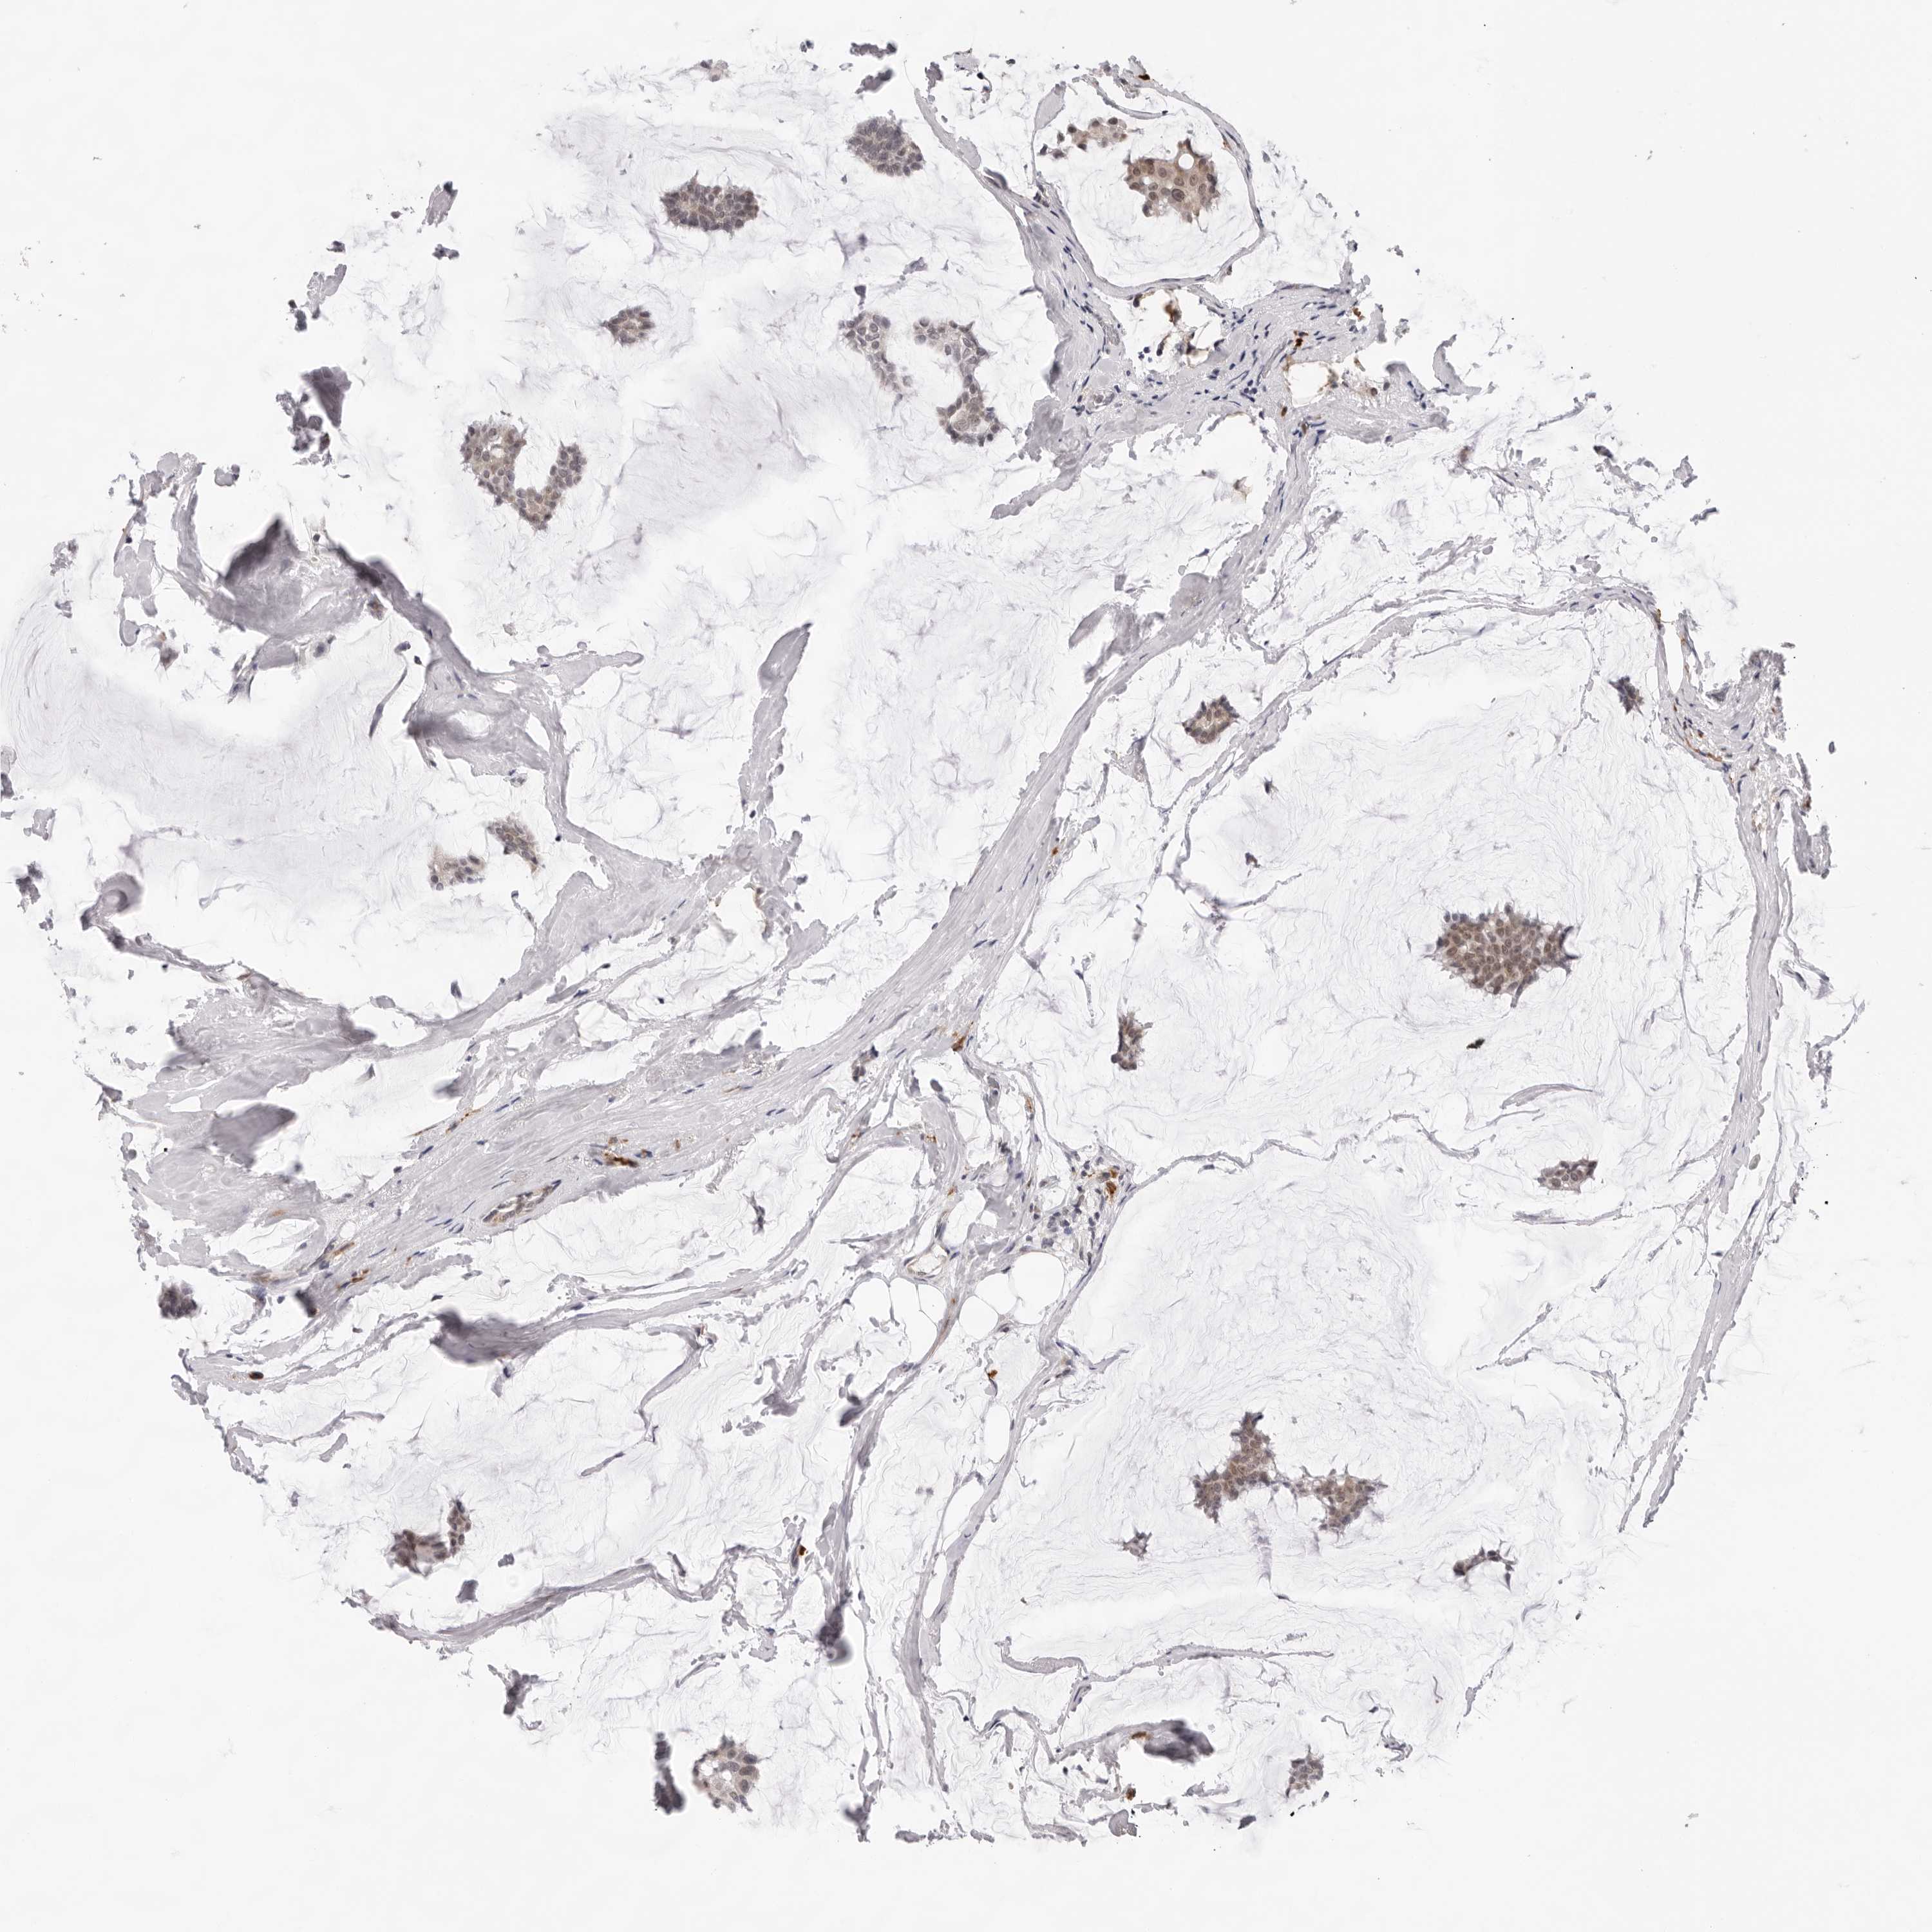

CANCER BREAST CANCER Show tissue menu

BRCA TCGA BRCA VALIDATION PROTEIN EXPRESSION

Breast cancer

Human cancer

Breast invasive carcinoma